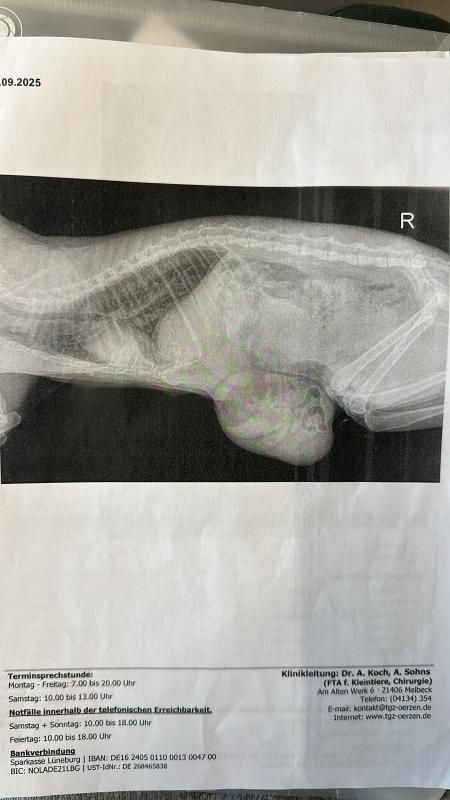

Hedwig kam am 16.09.25 zusammen mit ihren ca. 1 Tag alten Kitten zu uns ins Tierheim. Leider verstarben drei der insgesamt 4 Kitten in kürzester Zeit…Hedwig war aus gesundheitlichen Gründen nicht in der Lage, ihre Babys zu versorgen. Sie muss schon vor längerer Zeit einen Bauchdeckenbruch erlitten haben, in dem bereits Darmschlingen zu sehen waren. Hedwig wurde schnellstmöglich operiert, um sie endlich von den Schmerzen und Leiden zu befreien ! Nun muss sich das freundliche Mädchen erst wieder richtig erholen und ist dann auf der Suche nach einer tollen Familie, welche ihr ganz viel Liebe und Geborgenheit nach dieser furchbar schweren Zeit schenken möchte. Das letzte verbliebene Kitten „Zuma“ lebt übrigens bei einer Pflegestelle und wird mit dem Fläschchen aufgezogen…die kleine Motte entwickelt sich ganz toll !